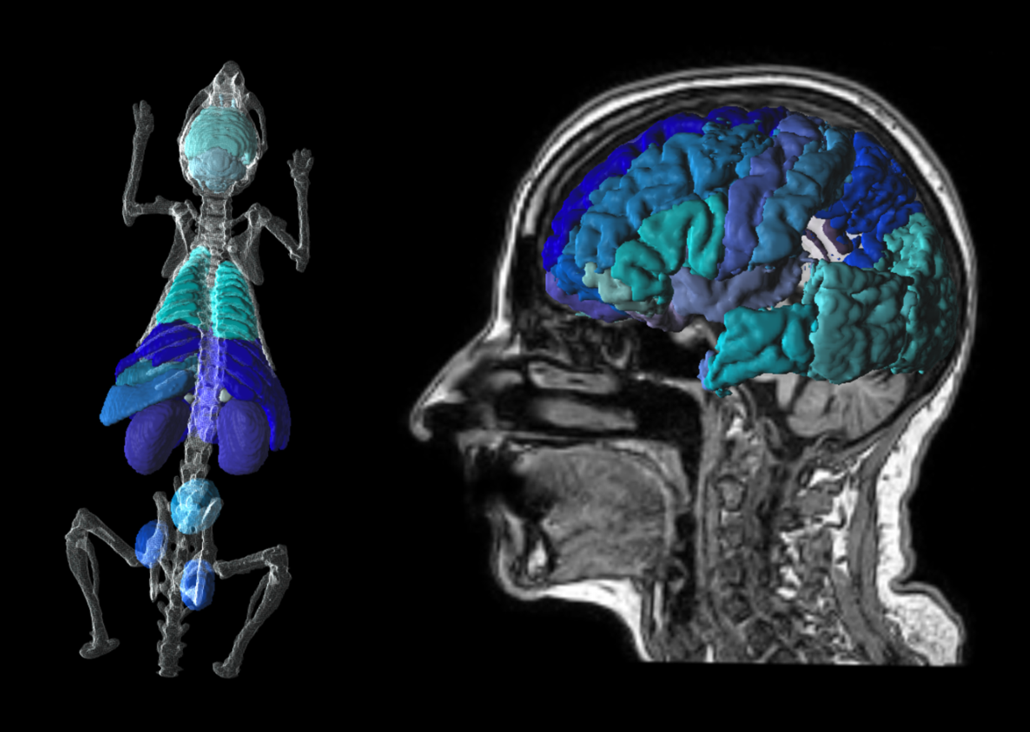

P3D Extended 3D Rendering

Translational tools to go from mouse to man. Easily transform atlases from template to individual space. Create stunning visuals for publication.

PNEURO Human Brain Analysis & Neurology Package

pmod’s PNEURO tool gives you streamlined segmentation for human brain PET and PET/MR and direct access to statistics, kinetic modelling & parametric mapping.